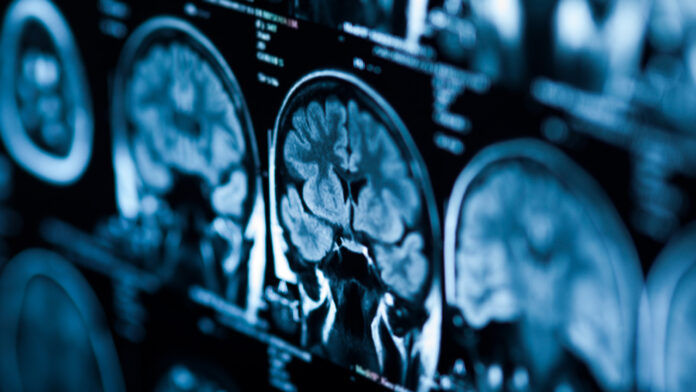

İngiltere’de yaşayan bir kadının duyduğu halüsinasyonlar, ona beynindeki tümörün tam yerini ve tedavi olması gereken hastanenin adresini söyledi. Doktorları şaşkına çeviren bu vaka, “iç sesin” hayatta kalmak için verdiği inanılmaz bir mücadeleye dönüştü.